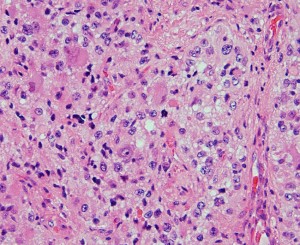

大小の神経細胞とグリア細胞が混在して存在します

小型のグリア細胞にも多少の異型があり腫瘍性グリアと考えられます

グレード1のgangliogliomaです

大脳皮質に大型の核を有する円形の神経細胞が散在しています。神経細胞間にグリア細胞がありますが腫瘍性増殖を示しません。MIB-1は1%以下でした。血管周囲にリンパ球浸潤があります。

構成要素はGFAP陽性の膠細胞が多く認められます。神経細胞様形態の細胞 ganglion cellではNeuN(+), CGA (+) synaptophisin (++), neurofilament (+)です。大型で腫大した核を有して核内封入体構造を有する好酸性もしくは淡明な細胞質を有する細胞が増殖してPXAを考えさせる部分像もありました。granular bodyも認められて,右の写真のように膠原線維の増生が目立つ部分もあります。これは表面の非常に硬い線維性の腫瘍部分です。MIB-1 indexは4%とやや高い値です。BRAF v600Eの変異が認められました。